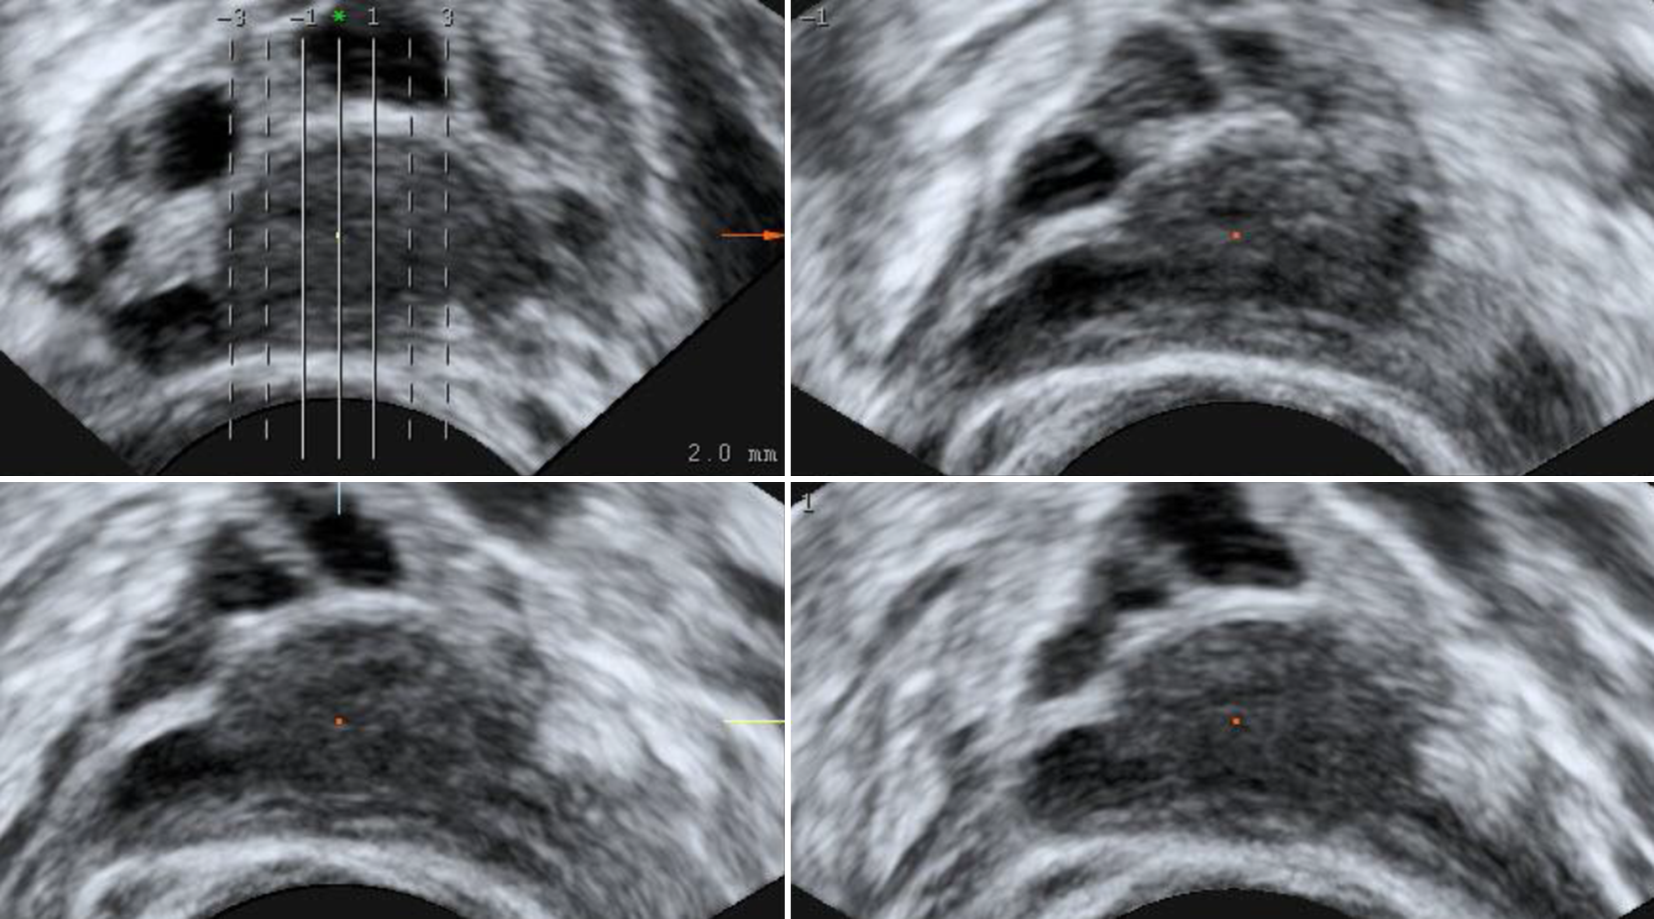

Abb. 5

Mit „tomographic ultrasound imaging“ lassen sich mehrere Bereiche eines Corpus luteum in Schnitten mit vorher festgelegter Größe durchmustern

Der 3‑D-Ultraschall kann bei der Darstellung des Corpus luteum diagnostisch durchaus hilfreich sein: Die Tomographic-ultrasound-Methode ermöglicht es, in vorher gewählten Abständen bis zu 9 Schnitte des Ovars nebeneinander am Bildschirm darzustellen und sich ein Bild von dem CL innerhalb des Ovars zu machen (Abb. 5). Die Sono-AVC™-Methode hat ihren idealen Einsatz in der ersten Zyklushälfte. Bei einem deutlich flüssigkeitsgefüllten Corpus luteum kann dieses als irregulär umrandete Struktur dargestellt werden (Abb. 6). Die manuelle 3‑D-Darstellung des Corpus luteum mit dem integrierten Grafikprogramm kann nur offline nach der eigentlichen Untersuchung durchgeführt werden. Der diagnostische Mehrwert ist begrenzt (Abb. 7; [2]).